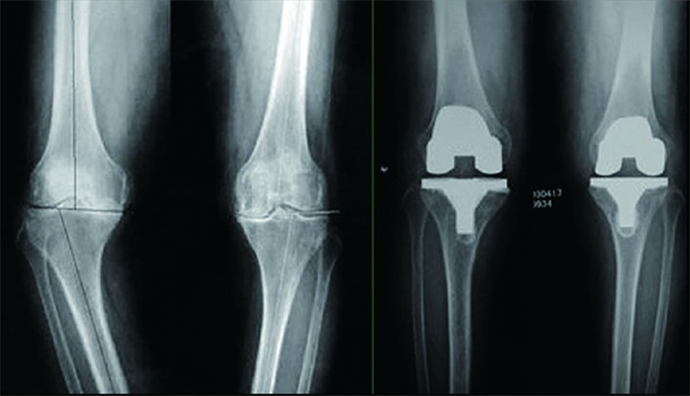

據(jù)了解,菏澤醫(yī)專(zhuān)附屬醫(yī)院骨外科目前開(kāi)展的股骨頸骨折FNS內(nèi)固定術(shù)、股骨粗隆間骨折PFBN內(nèi)固定術(shù)、骨盆骨折微創(chuàng)骶髂螺釘+infix內(nèi)固定術(shù)、骨盆骨折LC-2螺釘內(nèi)固定術(shù)、胸腰椎骨折經(jīng)皮椎弓根螺釘內(nèi)固定術(shù)、肩鎖關(guān)節(jié)脫位袢鋼板內(nèi)固定術(shù)、跗骨竇入路治療跟骨骨折、彈性髓內(nèi)釘治療兒童骨折、兒童肱骨髁上骨折閉合復(fù)位克氏針內(nèi)固定術(shù)、關(guān)節(jié)鏡下半月板修復(fù)、滑膜切除、脛骨髁間嵴骨折內(nèi)固定、肩袖撕裂修補(bǔ)等手術(shù)均是微創(chuàng)化手術(shù),不僅如此,在脊柱治療方面,骨外科開(kāi)展了UBE脊柱微創(chuàng)手術(shù),有效治療了椎間盤(pán)突出癥、椎管狹窄癥等疾病。此外,醫(yī)院還與著名矯形外科專(zhuān)家秦泗河成立“秦泗河名醫(yī)工作室”,是山東省殘聯(lián)指定菏澤唯一殘疾兒童矯形定點(diǎn)醫(yī)院?!肮峭饪婆c上級(jí)醫(yī)院聯(lián)系緊密,常年邀請(qǐng)國(guó)家級(jí)、省級(jí)專(zhuān)家來(lái)院坐診、手術(shù)?!?/span>孫全波介紹。

膝關(guān)節(jié)骨性關(guān)節(jié)炎行全膝關(guān)節(jié)置換術(shù)